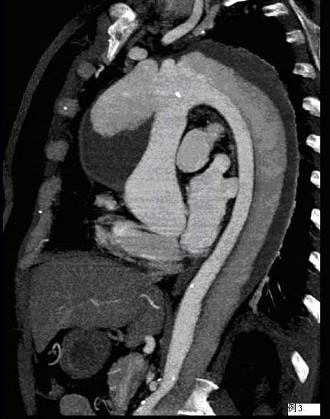

问题 请看一组主动脉的CT增强图像,正确的描述和结论是 ( )

选项 A、真腔较假腔小 B、真假腔之间线状低密度影为内膜片影 C、主动脉瘤 D、主动脉夹层 E、主动脉血栓 一、多项选择题

答案 ABD